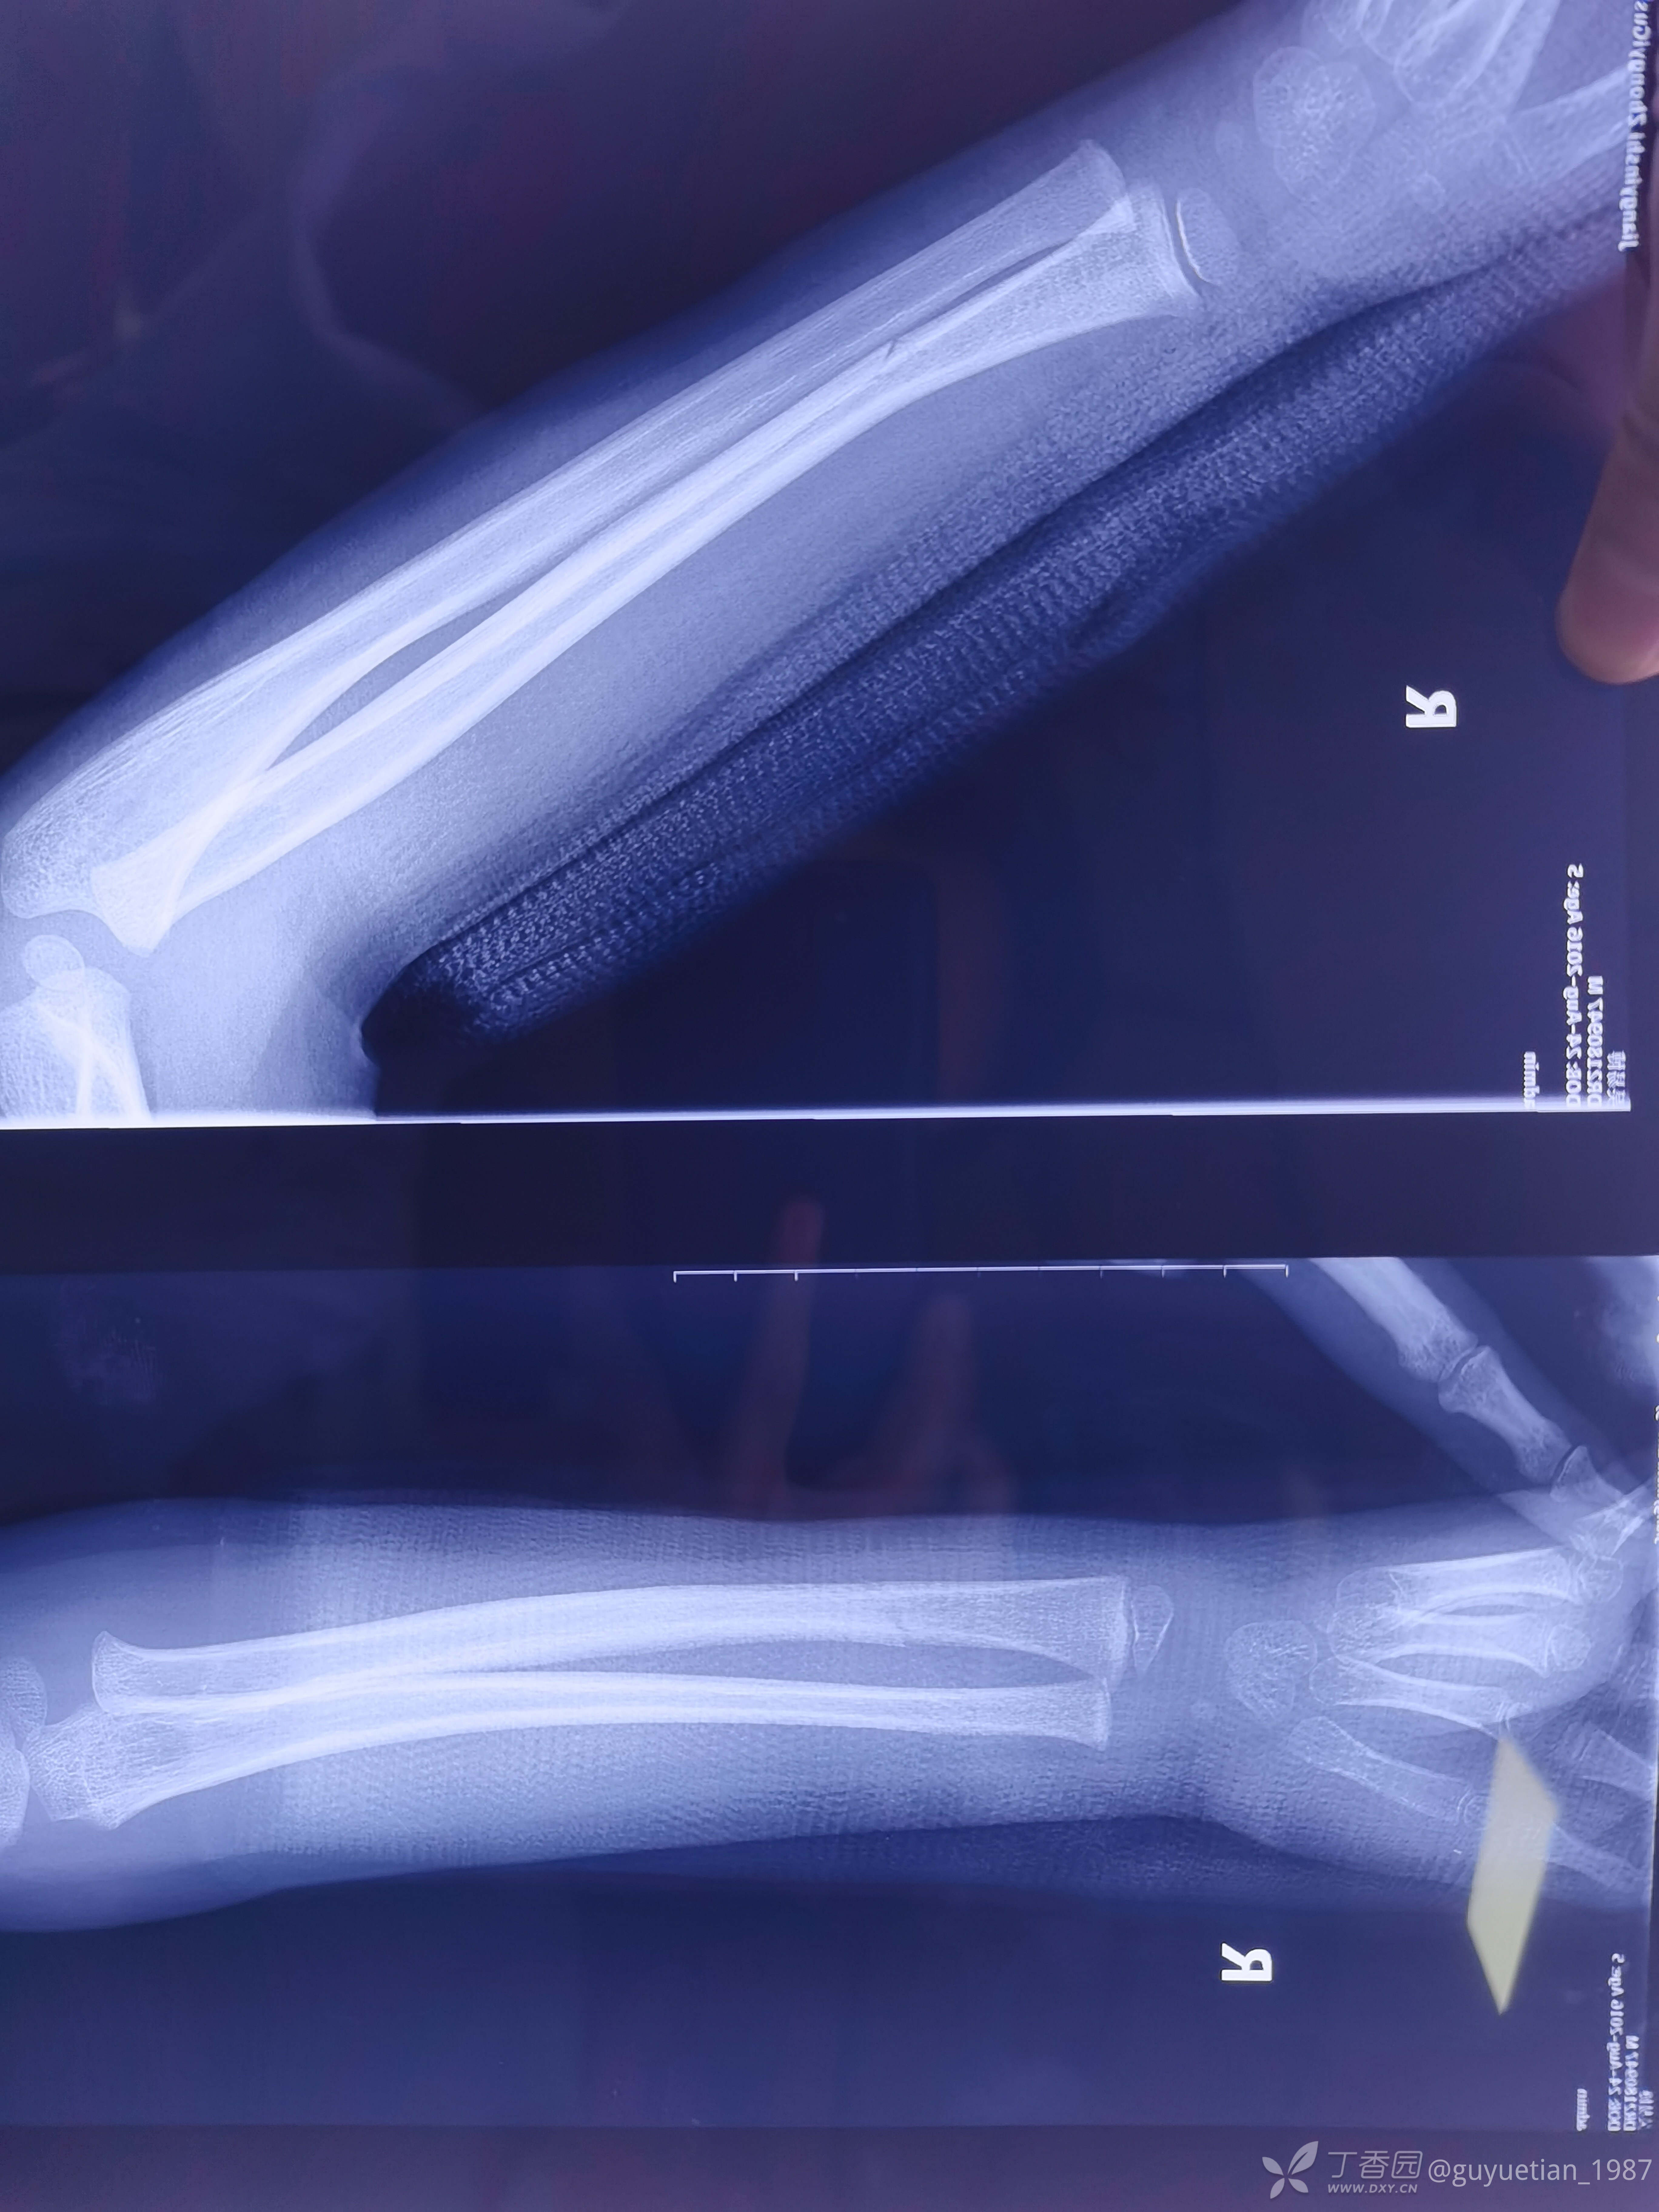

3周后,明显看到骨痂,开始塑形。

5周后复诊,解除夹板固定。塑形可以,外观正常。

7周后复诊